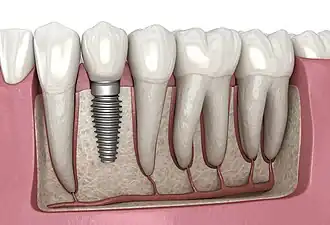

A dental implant (also known as an endosseous implant or fixture) is a prosthesis that interfaces with the bone of the jaw or skull to support a dental prosthesis such as a crown, bridge, denture, or facial prosthesis or to act as an orthodontic anchor. The basis for modern dental implants is a biological process called osseointegration, in which materials such as titanium or zirconia form an intimate bond to the bone.[1] The implant fixture is first placed so that it is likely to osseointegrate, then a dental prosthetic is added. A variable amount of healing time is required for osseointegration before either the dental prosthetic (a tooth, bridge, or denture) is attached to the implant or an abutment is placed which will hold a dental prosthetic or crown.

Single tooth restorations are individual freestanding units not connected to other teeth or implants, used to replace missing individual teeth.[23] For individual tooth replacement, an implant abutment is first secured to the implant with an abutment screw. A crown (the dental prosthesis) is then connected to the abutment with dental cement, a small screw, or fused with the abutment as one piece during fabrication.[28]: 211–232  Dental implants, in the same way, can also be used to retain a multiple tooth dental prosthesis either in the form of a fixed bridge or removable dentures.